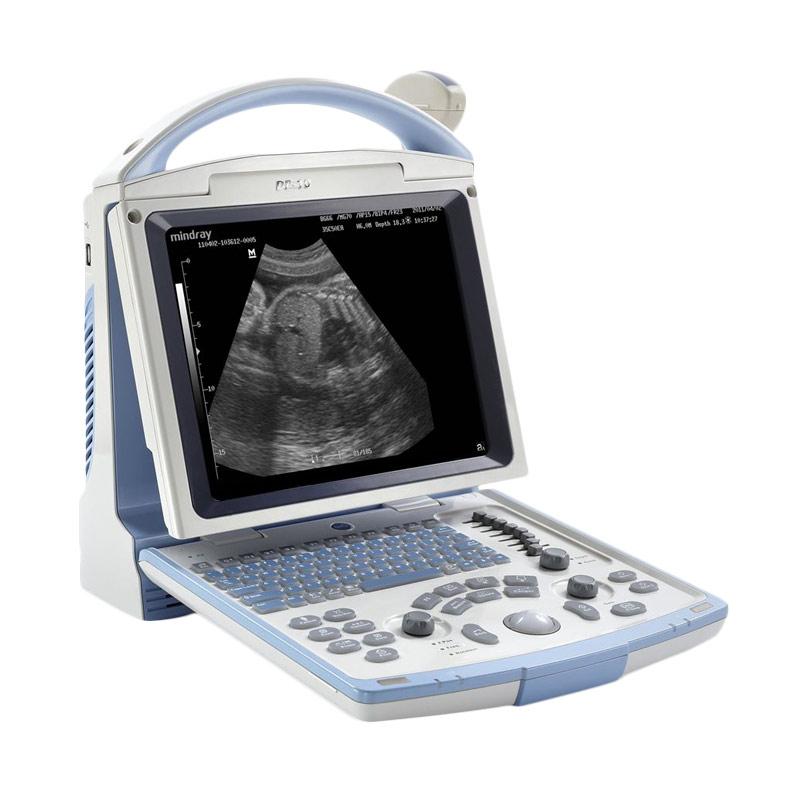

Jual Mindray Original Dp 50 Alat Usg B W 2d 2 Dimensi Terbaru November 2021 Harga Murah Kualitas Terjamin Blibli

Jual Mindray Original Dp 50 Alat Usg B W 2d 2 Dimensi Terbaru November 2021 Harga Murah Kualitas Terjamin Blibli

Alat Usg Portable 2 Dimensi Plazadiagnostik

Alat Usg Portable 2 Dimensi Plazadiagnostik

Jual Mesin Usg 2 Dimensi Mindray Toko Alat Rumah Sakit

Jual Mesin Usg 2 Dimensi Mindray Toko Alat Rumah Sakit